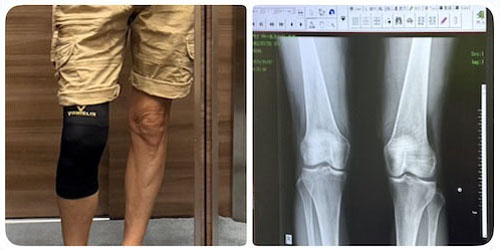

Runner's Knee

千駄谷の「せんだがや整形外科」へ。

2週間ほど続いている右膝の外側の違和感&痛みに関して。

問診およびX線写真から、大腿二頭筋(だいたいしとうきん:ハムストリングスのひとつ)から伸びた筋肉の筋に炎症が起きていると診断。いわゆる Runner’s Knee. 腸脛靭帯炎(ちょうけいじんたいえん)とも言われるらしい。クリニックの治療としては、筋肉の緊張を和らげる治療で消炎鎮痛の湿布テープの処方。また、リハビリテーション(PTのことらしい)を勧められたので今週と再来週に予約。一回20〜30分とのこと。

オーバーユースに起因がある傷害なので、使わない(膝に負荷のかかる運動はサスペンド)、というわたしの判断は正しかった。基本的に一般的な炎症と同じRICEだ。